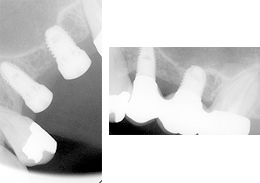

ショートインプラント使用し骨造成をしないグラフト術式

- 治療内容

- 抜歯から3ヶ月の治癒期間を経てCT撮影を行った結果、通常であれば上顎洞挙上手術の対象となるケースが多いが、ショートインプラントを用いることで大規模な骨造成お回避できることがわかった。2本ショートインプラント埋入

当院では、ショートインプラントを起用する場合には、術前にCT撮影を行い、3Dコンピュータシミュレーション(ノーベルクリニシャン)システムを用い、精密な診断・インプラント治療設計を行った上で、確実に、そして安全にショートインプラント治療を行っております。

沼澤歯科Southインプラントセンター小金井では、事前にCT撮影・3Dコンピュータシミュレーション(ノーベルクリニシャン)システムを使用し、骨の状態を正確に把握することで精度が高いインプラントの傾斜埋入ができます。